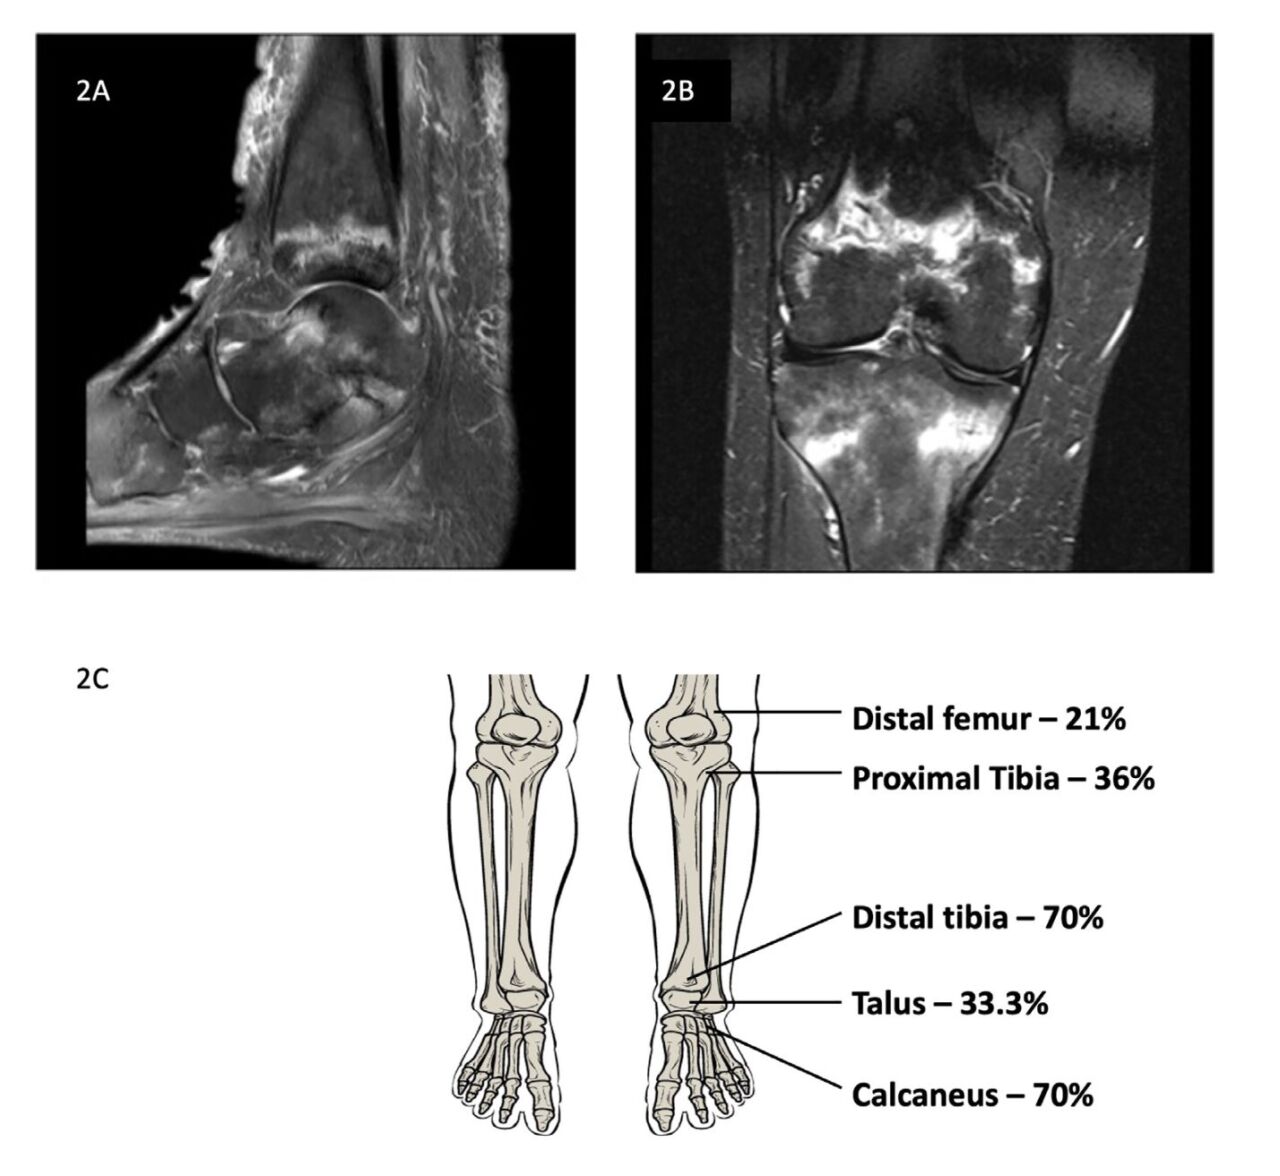

メトトレキサート関連脆弱性骨折(Methotrexate osteopathy: MTXO)は、低用量MTXを長期使用しているリウマチ患者においておきる下肢の骨折として報告されている。骨折のパターンは特徴的で、MRIで帯状または曲線状の不全骨折線を示し、遅れて診断されやすい。

・MTXOはMRIなどの高精度画像検査による早期診断が重要。

画像を見る限りは脆弱性骨折のようなもので、おそらくMRIを撮らないとわからないものなんでしょう。特徴的な帯状のバンドがでるようです。見たら異常とは気づきますがこれがメトトレキサートによるのだと気づくには知っていなければ無理ですよね・・・でも知っていれば一発診断。こういうのは勉強しておくしかないです。